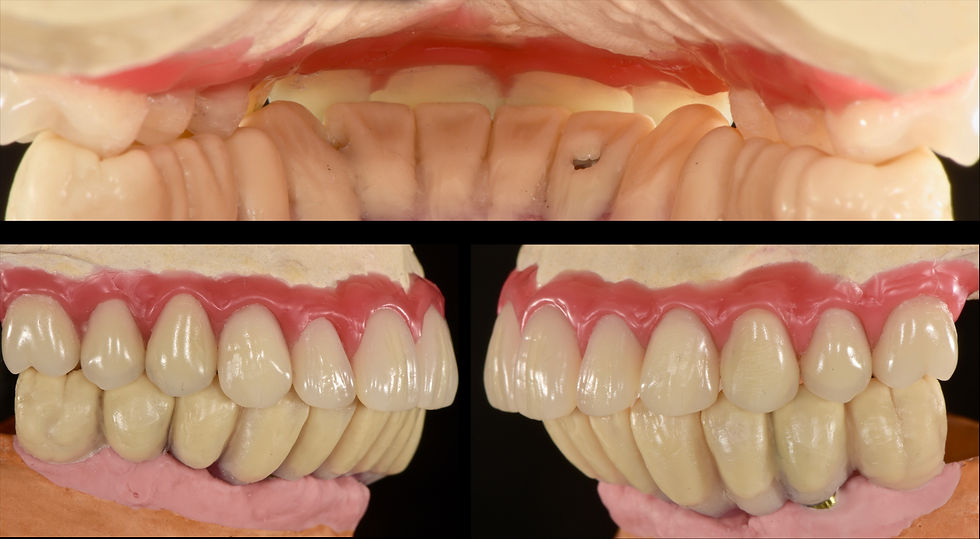

Vision of the interrelationships between jaws: the II prosthetic class was brought to the I class in the cusp-fossa so that no movements of the upper prosthesis were generated

Verification of interarch relations on the model